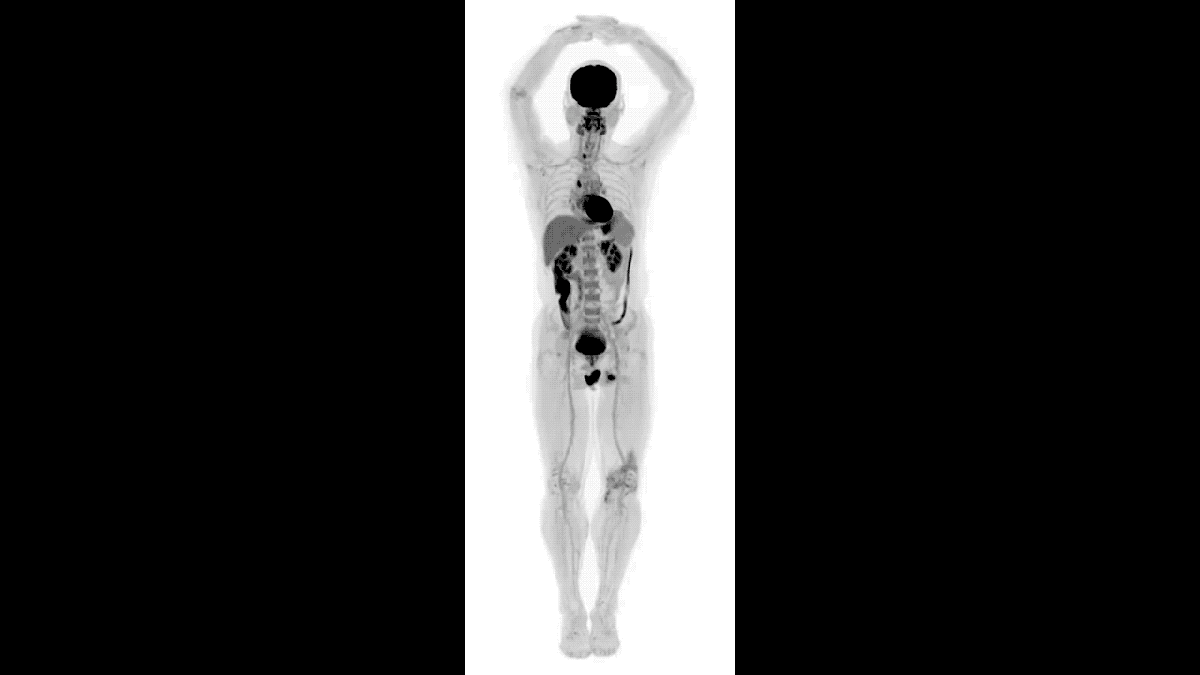

New 3D body scanner uses 40 times less radiation than PET scans

• New medical imager captures unprecedented 3D images of the human body.

• It’s 40 times faster than PET scans, and can use 40 times less radiation.

• EXPLORER scanner makes PET and CT scans look old-fashioned.

What do you get if you combine the technologies on which the two most successful medical imaging devices — positron emission tomography (PET) and x-ray computed tomography (CT) — are based? You get EXPLORER, the stunning new scanner that can capture an amazingly detailed 3D image of the entire human body in 20–30 seconds.

EXPLORER is 40 times as fast as a PET scanner, making it more feasible to do repeated studies on an individual, and, of course, there are the movies that can provide an unprecedented look at the in-body progress of radiotraceable agents. EXPLORER’S also 40 times more sensitive than PET scanners, so it will cause patients to be exposed to far less radiation during diagnosis than traditional PET or CT scans.